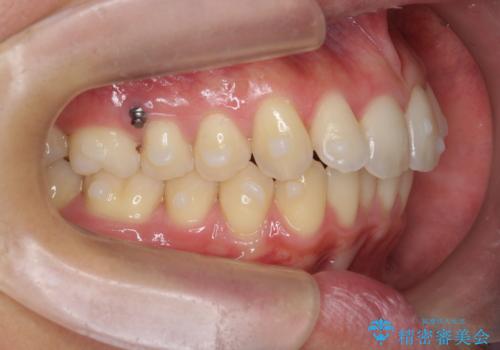

過蓋咬合・上顎前突・叢生を改善するマウスピース矯正

- 前歯のがたつき、不揃いさの改善を求めて来院されました。

・前歯の深い噛み合わせ (過蓋咬合)

・上顎前突(Angle Class2)

・叢生(がたつき)

以上のような問題点をマウスピース矯正インビザラインとマイクロインプラントを用いて矯正治療を行い改善して行きます。

20時間以上のマウスピース装着、ゴムかけを遵守していただいたおかげでしっかりと噛み合わせ、がたつきの改善を行うことができました。